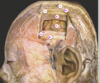

State what type of herniation A-D are [4]

A: **Cingulate** (Subfalcine) B: **Central** (**transtentorial**) C: **Uncal** D: Downward cerebellar (**Tonsillar**)